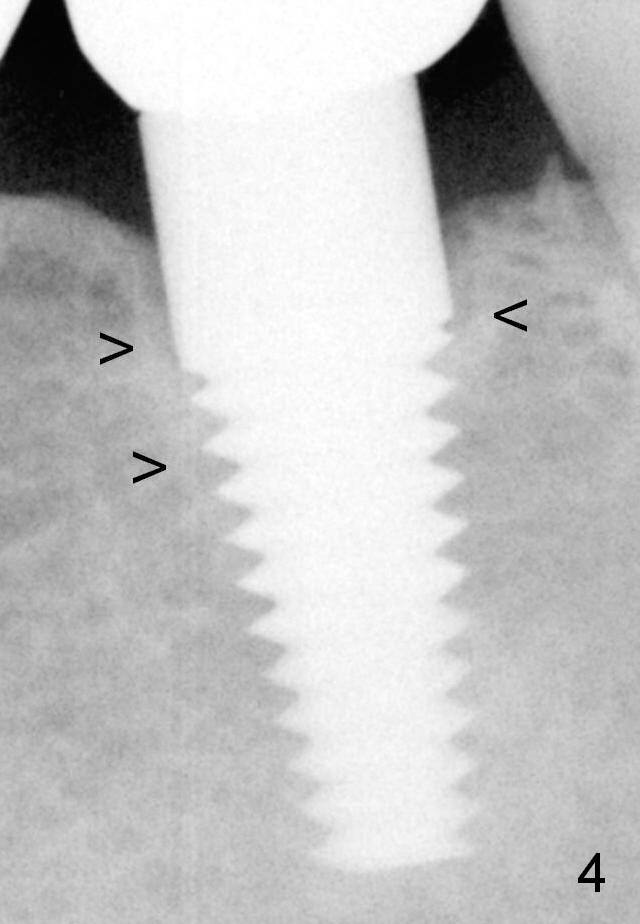

Fig.4: 3 years postop (1 year post cementation) with formation of cortical bone around the implant (arrowheads).

Cortical Formation Around Implant